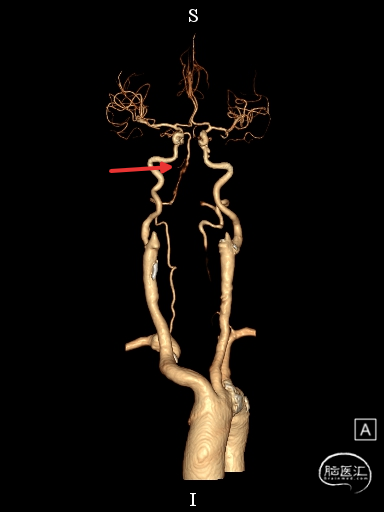

术前DSA影像

右侧颈内动脉起始部中度狭窄,未见血流向后循环代偿。

左侧颈内动脉造影提示后交通开放,代偿供应后循环。

左侧椎动脉开口重度狭窄,前向血流缓慢,V4闭塞。

左侧椎动脉V4段闭塞、左侧椎动脉起始部重度狭窄、左侧小脑急性脑梗塞、右侧颈内动脉起始部狭窄。